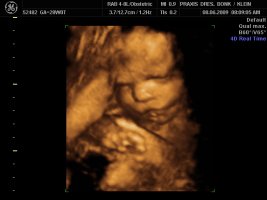

Und dann haben wir endlich unser Video gemacht, Zeit hatten wir ja nun genug und das ist voll süß geworden, sie war wohl auch wie Mama müde, denn sie hatte öfter mal gegähnt und mit den Augen geblinzelt :love1 ...kann es kaum noch erwarten die Kleine in die Arme zu nehmen :applaus

Und wir haben endlich ein Beweisfoto bekommen, dass es ein Mädchen ist...

Hier ein paar Bilder von Montag, neben dem Video haben wir auch sehr viele Bilder mitbekommen.... :love1

Anhänge

• Bild 1.jpg

Bild 1.jpg

72,4 KB · Aufrufe: 72

• Bild2.jpg

Bild2.jpg

75,1 KB · Aufrufe: 72

• Bild3.jpg

Bild3.jpg

61,5 KB · Aufrufe: 72

@Imke ui was für schöne Bilder, will auch! *jammer*